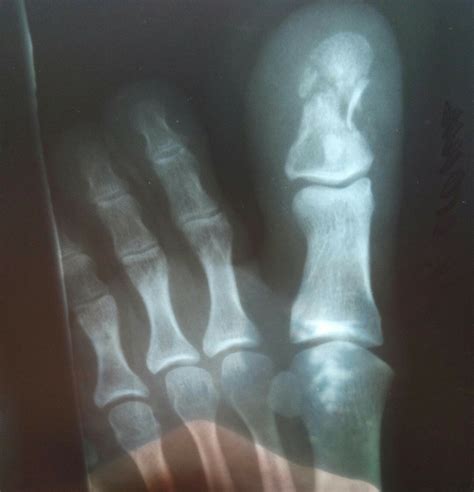

Перелом Пальца На Ноге Фото — Фото Картинки

Как выглядит перелом пальца на ноге фото